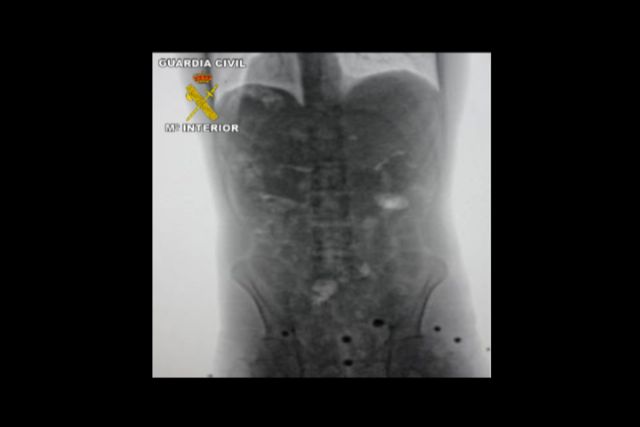

La Guardia Civil en el marco de la operación "CÁPSULA" ha desarticulado una organización internacional dedicada a la introducción de cocaína en España utilizando mulas que la transportaban en el interior de su organismo. La operación se ha saldado con la detención de los 23 integrantes de la red, entre los que se encuentra su cabecilla, afincado en Bolivia, país desde donde se enviaba la droga.

La investigación se inició en febrero de 2012 cuando una persona denunció la muerte de un vecino de Águilas (Murcia), que presuntamente había sido contratado por otras personas para que realizara viajes a Bolivia con la intención de introducir en España cocaína en el interior de su cuerpo. Esta persona falleció en Bolivia porque dos de los envases de cocaína que transportaba se rompieron.

Tras las primeras pesquisas se obtuvieron indicios que permitieron judicializar la investigación, que dio sus primeros frutos unos meses más tarde cuando la Guardia Civil detuvo a cuatro personas en Madrid que trasladaban hasta Murcia más de medio kilo de cocaína de gran pureza. Seguidamente, en Barajas, se interceptó y detuvo a otras dos personas que realizaban la misión de mulas, ya que importaban desde Bolivia un kilo de cocaína cada uno en el interior de su cuerpo.

Por otro lado, en la prisión de Palmasola, ubicada en Santa Cruz de la Sierra, se procedió a tomar declaración a una interna de origen español que fue captada por la organización investigada y, posteriormente, detenida cuando pretendía salir del país con destino a España como mula, ya que transportaba en el interior de su cuerpo un kilo de cocaína.